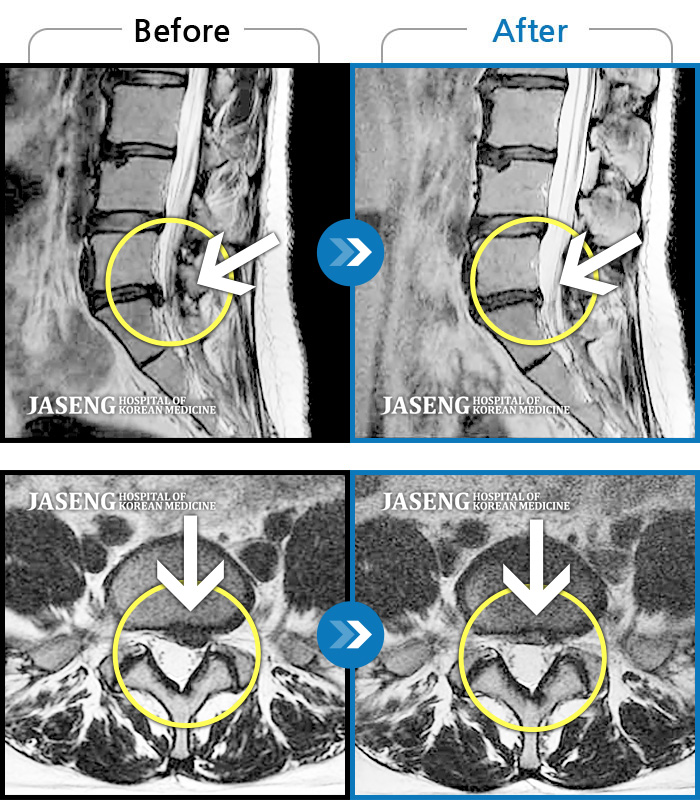

허리디스크

잠실 · 한상욱 원장

허리가 많이 아프고 왼쪽 다리가 저려 움직이기가 힘들다.

촬영시기

2022.01.19 ~ 2022.11.14

2022.12.02